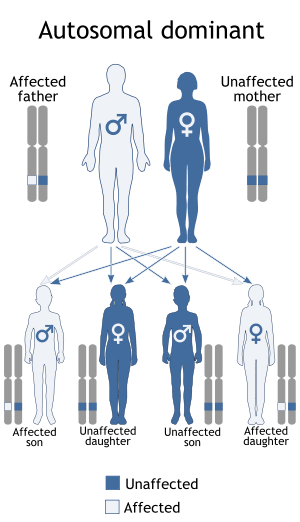

When inherited, multiple endocrine neoplasia type 2 is transmitted in an autosomal dominant pattern, which means affected people have one affected parent, and possibly-affected siblings and children. Some cases, however, result from spontaneous new mutations in the RET gene. These cases occur in people with no family history of the disorder. In MEN2B, for example, about half of all cases arise as spontaneous new mutations.